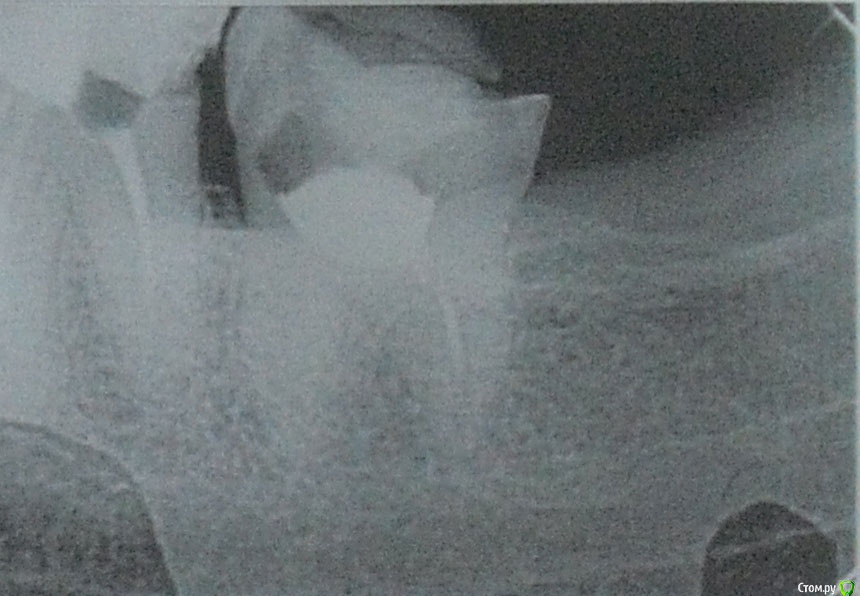

usersha Опубликовано 1 августа, 2019 Поделиться Опубликовано 1 августа, 2019 Здравствуйте! 10 дней назад у меня выступил флюс то есть десна между 7 и 8 зубом слева внизу отекла и появился гнойничек. До этого была боль пульсирующая или как будто распирающая. После того появился флюс боль практически прошла. У врача на приеме сделали снимок. Я думала что причина в 8 зубе так как боль усиливалась при нажатии. Но потом когда боль прошла то и при нажатии боли нет. По снимку врач сказала что корни нормальные и проблема в десне может быть поранила. Хирург сделал надрез сказал чтобы выходила инфекция. Дренаж не ставил. Я полоскала содой солью и пила амоксициллин 8 дней. Отек стал спадать было видно как образуется гнойное типа налета и выходит..... где то дня 4 назад десна стала немного побаливать и я добавила левомеколь - 3 раза в день... и периодически из этого надреза появляется белый налет (гной) потом при полоскании отскакивает. Опухоль в основном спала,но десна слегка увеличена. В основном десна не болит если не теребить ее. Как долго выходит инфекция и проходит флюс? Вторая неделя пошла это долго или это нормальные сроки? И еще вопрос. Пломба у 7 зуба стоит так что с внутренней стороны межзубное пространство забито пломбой и она упирается в десну. Я прочитала что нависающий край пломбы может травмировать десну. Один из способов проверить - зубная нить которая не должна цепляться. Как раз если провести нитью то у самой десны нить как бы цепляется как за крючок что ли. Могла ли эта пломба в межзубном пространстве давящая на десну привести к флюсу? Сейчас там где с внутренней стороны пломба давит в межзубном пространстве я чувствую дискомфорт и немного болезненно у десны. Флюс у меня с внешней стороны ( то есть со стороны щеки) он был расположен как-то прям между зубами 7 и 8 со смещением отечности в сторону 8 зуба. Может ли врач убрать пломбу в межзубном пространстве нависающий край без переделывания всей пломбы? Заранее большое спасибо за помощь! PS первый снимок 7 и 8 зубы, второй снимок 7 зуб и часть 8 Ссылка на комментарий

red_butler Опубликовано 2 августа, 2019 Поделиться Опубликовано 2 августа, 2019 Спасибо за ответ! Скажите а зачем удалять зуб мудрости если он не болит и как сказала врач там корни нормальные? флюс скорее от травмы либо зубной щеткой десны либо от постоянного пломбы в межзубном пространствеВосьмой зуб сильно разрушен, корневые каналы полноценно не пролечены. Контактного пункта с седьмым зубом нет, это привело к воспалению десны и рецидиву кариеса на седьмом зубе. Оставляя зуб мудрости Вы приближаете конец седьмого зуба. 2 Ссылка на комментарий